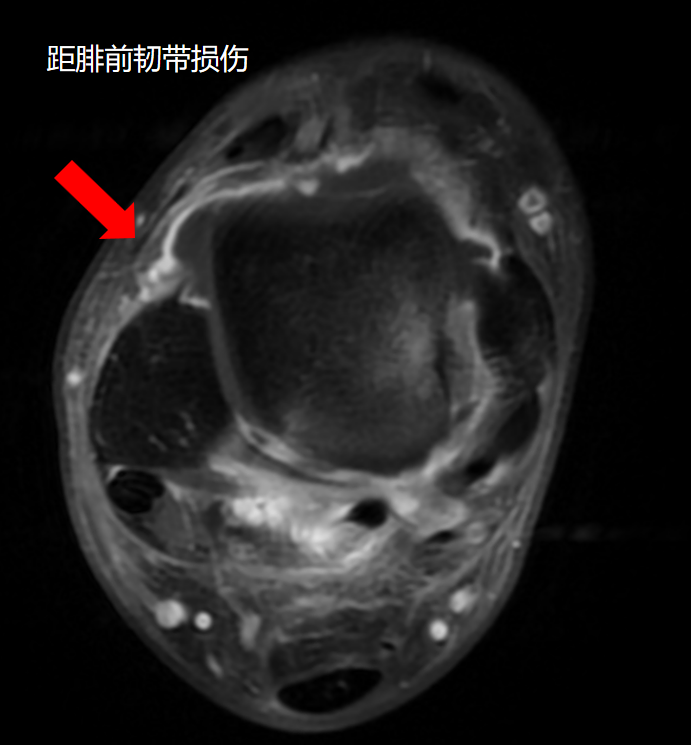

经查体,该患者右踝关节前抽屉试验阳性,内翻应力实验阳性,前外侧关节间隙压痛。踝关节距腓前韧带失效,踝关节不稳明显。完善踝关节DR及MRI检查。

根据病情决定行关节镜下右踝关节腔探查清理+外侧副韧带修复+距骨病灶清除+自体骨软骨移植术。